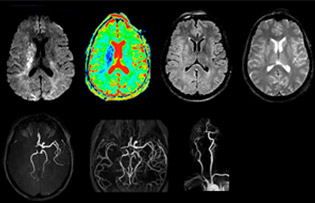

“In France, stroke is usually imaged with MRI, not CT, even for emergency treatment. This is because MRI helps us directly visualize ischemia in the acute phase, but can also help rule out differentials such as MS and hematoma. In addition, we can assess the intracranial and extracranial vessels during the same examination,” says Dr. Savatovsky.

The first challenge in MRI of stroke is speed. The patient typically arrives from an ambulance in the MRI preparation room and the installation is done on a separate dock outside the scanner room. “The venous access is placed during the neurological examination. If the delay from the first symptoms allows the patient to receive thrombolysis we do a very fast examination that typically lasts about 11 minutes including the pre-scans. In the case of transient ischemic stroke we usually add ASL perfusion because in some symptoms with negative diffusion, ASL sometimes indicates a vascular origin.”

“Ingenia provides great flexibility in the parameters setting. We can tune a sequence the way we want,” says Dr. Savatovsky. “For example, in a stroke exam we use a FLAIR sequence of about two minutes instead of the four-minute FLAIR we use for MS. The diffusion is 30 seconds, the T2*-weighted scan is 30 seconds, the angiography scan time is less than one minute. Ingenia is a great scanner in that situation; even with these fast sequences we can achieve good images with good SNR. When the first sequence tells us that it’s not an ischemic stroke but a hemorrhagic stroke, we may switch to a time-resolved angiography to look for vascular malformations and venous thrombosis.

“Every center is different, but for me the ideal protocol for stroke includes diffusion weighted imaging, FLAIR, and fast susceptibility imaging,” says Dr. Savatovsky. “Our fast susceptibility weighted imaging takes 50 seconds, so it’s as fast as T2*-weighted imaging. It visualizes hemorrhage but also the clots. We also do 3D MR angiography that provides information on cervical and brain vessels. If the patient does not need immediate treatment, or if additional information is needed to decide on treatment, we might also add perfusion imaging and post-contrast T1-weighted imaging.”